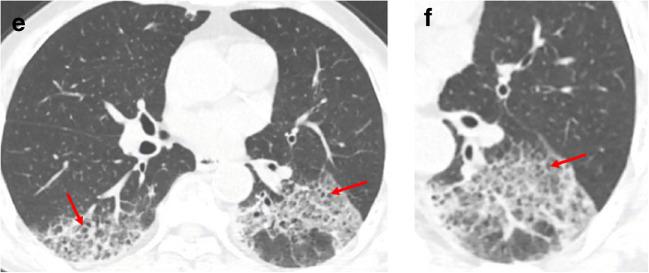

The majority of infected patients had a history of exposure in Wuhan or to infected patients and mostly presented with fever and cough. More than half of the patients presented bilateral, multifocal lung lesions, with peripheral distribution, and 53 (59%) patients had more than two lobes involved. Of all included patients, COVID-19 pneumonia presented with ground glass opacities in 65 (72%), consolidation in 12 (13%), crazy paving pattern in 11 (12%), interlobular thickening in 33 (37%), adjacent pleura thickening in 50 (56%), and linear opacities combined in 55 (61%). Pleural effusion, pericardial effusion, and lymphadenopathy were uncommon findings. In addition, baseline chest CT did not show any abnormalities in 21 patients (23%), but 3 patients presented bilateral ground glass opacities on the second CT after 3-4 days.

SARS-CoV-2 infection can be confirmed based on the patient's history, clinical manifestations, imaging characteristics, and laboratory tests. Chest CT examination plays an important role in the initial diagnosis of the novel coronavirus pneumonia. Multiple patchy ground glass opacities in bilateral multiple lobular with periphery distribution are typical chest CT imaging features of the COVID-19 pneumonia.

大多数感染患者有武汉接触史或感染患者接触史,主要表现为发热和咳嗽。超过一半的患者表现为双侧、多灶性肺部病变,呈外周分布,53 例(59%)患者有两个以上肺叶受累。所有纳入患者中,COVID-19 肺炎 65 例(72%)表现为磨玻璃影,12 例(13%)为实变,11 例(12%)为铺路石征,33 例(37%)为小叶间隔增厚,50 例(56%)为邻近胸膜增厚,55 例(61%)为线状混浊合并。胸腔积液、心包积液和淋巴结病少见。此外,21 例患者(23%)基线胸部 CT 无任何异常,但 3 例患者在第 3-4 天后第二次 CT 检查时出现双侧磨玻璃影。

根据患者的病史、临床表现、影像学特征和实验室检查可以确诊 SARS-CoV-2 感染。胸部 CT 检查在新型冠状病毒肺炎的初步诊断中起重要作用。双侧多发性肺叶多灶性分布的多发性斑片状磨玻璃影是 COVID-19 肺炎的典型胸部 CT 影像学特征。